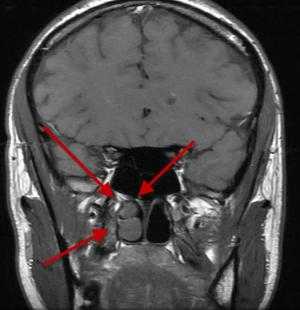

Аденома может воздействовать на окружающие ткани, сдавливая нервные окончания и затрудняя диагностику заболеваний головного мозга. Новообразование располагается в области турецкого седла, но возможно прорастание опухоли в костные пазухи, желудочки головного мозга, базальную поверхность больших полушарий. На фото тонких срезов изучаемой зоны все эти патологические изменения хорошо видны. МРТ показывает границы и локализацию опухоли гипофиза, помогает классифицировать новообразование и назначить результативное лечение.

Наиболее часто на томограммах обнаруживают аденому гипофиза - доброкачественное новообразование, исходящее из передней доли. Опухоли могут произрастать из любого отдела питуитарной железы, что вызывает многообразие клинических проявлений. Аденома гипофиза локализуется в области турецкого седла, при значительном росте возможно распространение на костные пазухи, желудочки головного мозга, базальную поверхность больших полушарий. Вышеописанные структуры врач может рассматривать в виде многоплоскостных объемных изображений, состоящих из множества срезов, что позволяет уточнить:

- размеры и границы опухоли;

- ее взаимосвязь с окружающими структурами - супраселлярной и мозговой цистернами, перекрестом зрительных нервов, пазухой основной кости, спинкой и бугорком седла, кавернозными синусами и пр.;

- предположительный характер (доброкачественный или злокачественный, первичный или метастатический, окончательная верификация доступна после морфологического исследования). Анализируют постконтрастные снимки, интенсивность накопления красителя (аденомы в подавляющем большинстве задерживают препарат медленнее, чем ткани гипофиза, для злокачественных опухолей характерен усиленный ангиогенез). Дифференциацию проводят с краниофарингиомой, кистой кармана Ратке и арахноидальной жидкостной полостью, имеющих схожие признаки на МР-сканах.

Специалист делает вывод о наличии новообразования гипофиза при обнаружении деформации дна одноименной ямки, асимметрии самой железы, неоднородности ее структуры, смещении воронки от срединной линии.